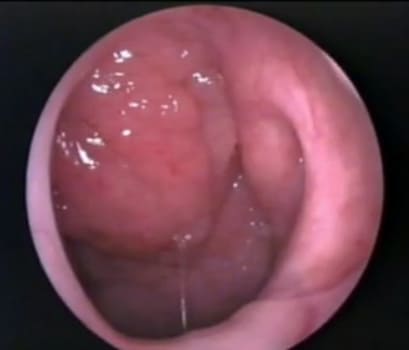

Аденоиды 1 степени, фото через эндоскоп

Клиническая картина (выраженность патологических изменений) не всегда соответствует степени увеличения аденоидов. Бывает так, что аденоиды первой и второй степени могут вызывать сильное затруднение носового дыхания, резкое снижение слуха, а аденоиды третей степени не вызывают видимых нарушений. Поэтому только по размеру однозначно нельзя сказать, что нужно делать – лечить консервативно или радикально (удалять аденоиды).